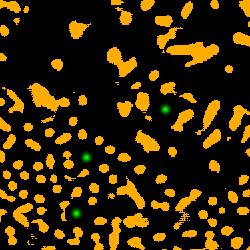

4.1.1 Voronoi labels

A Voronoi diagram is a partitioning of a plane into convex polygons (Voronoi cells) according to the distance to a set of points in the plane. There is exactly one point (seed point) in each cell and all points in a cell are closer to its seed point than other seed points. In our task, the detected points in an image can be treated as seed points to calculate the Voronoi diagram as shown in Fig. 1(b). For each Voronoi cell, assuming that the corresponding nucleus is located within the cell, then the Voronoi edges separate all nuclei well and the edge pixels belong to the background. This assumption holds for most of the nuclei because the detected points are around the centers and nuclear shapes are nearly convex (Fig. 3(b)).

Assigning the Voronoi edges as background pixels and the detected points (dilated with a disk kernel of radius 2) as nuclei pixels, we obtain the Voronoi point-edge label (Fig. 3). All other pixels are ignored during training. Note that although the pixels on the Voronoi edge between two touching nuclei may not necessarily be background, the edges are still helpful in guiding the network to separate the nuclei. The Voronoi labels aim to segment the central parts of nuclei and are not able to extract the full masks, because they lack the information of nuclear boundaries and shapes. To overcome this weakness, we generate another kind of labels that contain this complementary information.

4.1.2 Cluster labels

Considering the color difference between nuclei and background pixels, it is feasible to perform a rough segmentation using clustering methods. We choose -means clustering to extract both nuclei and background pixels from the image, and generate the cluster labels. Given an image with pixels (), -means clustering aims to partition the pixels into clusters according to the feature vector of each pixel , such that the sum of within-cluster variances is minimized:

| (4) |

We use -means to divide all pixels into clusters: nuclei, background and ignored. The cluster that has maximum overlap with points label is considered as nuclei, and the cluster that has minimum overlap with the dilated points label is considered as background. The remaining one is the ignored class. The pixels of the ignored class are often located around the nuclear boundaries, which are hard for a clustering method to assign correct labels.

For the feature vector , color is a straightforward choice. However, clustering with color will result in wrong assignments for pixels inside some nuclei that have non-uniform colors. To cope with this issue, we add a distance feature. In a distance map (Fig. 3(c)), each value indicates the distance of that pixel to the closest nuclear point and therefore incorporates the spatial information. In particular, the pixels that belong to nuclei should be close enough to points in the label while background pixels are relatively far from those points. The distance map can be calculated by the distance transform of the complement image of detected points. Combining the distance value with the RGB color values as the feature vector in -means clustering, we obtain the initial cluster labels. is the clipped value by truncating large values to 20 and , , are normalized values such that every feature has similar value range.

The cluster label (Fig. 1(b)) is generated by refining the clustering result with morphological dilation and erosion, which are done separately in each Voronoi cell to avoid connecting close nuclei. The cluster labels have more shape information about the nuclei compared with the Voronoi labels, at the expense of more errors and uncertainties. We argue that these two types of labels are complementary to each other and will jointly lead to better results.